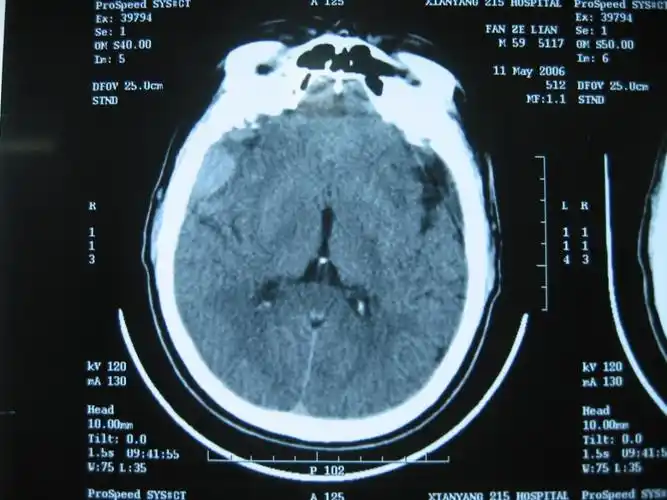

67超急性期大面积脑梗死ct平扫表现

▎头颅ct平扫有高血压病史10年,最高血压190/100mmhg,目前口服药物